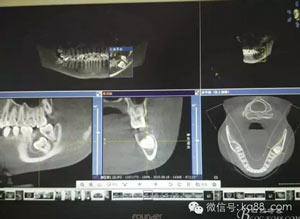

圖1.術(shù)前患者的全景片影像檢查情況:37未萌出,牙冠周圍有囊性陰影,牙根接近下頜骨皮質(zhì)骨邊緣。

圖5.CBCT檢 查:下頜管位于38牙根的舌側(cè)。給手術(shù)提供避免損傷神經(jīng)的可靠保證。